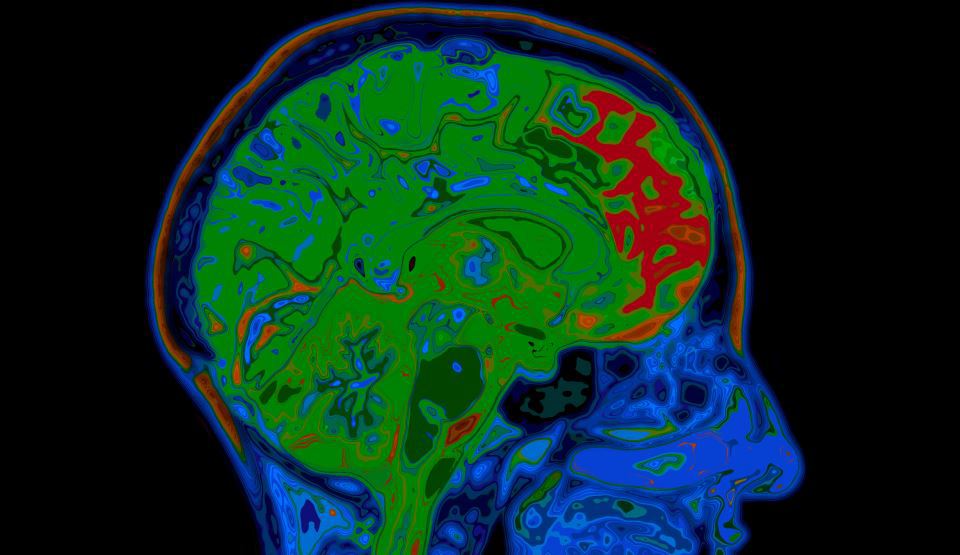

20 de lucruri uimitoare despre creierul uman